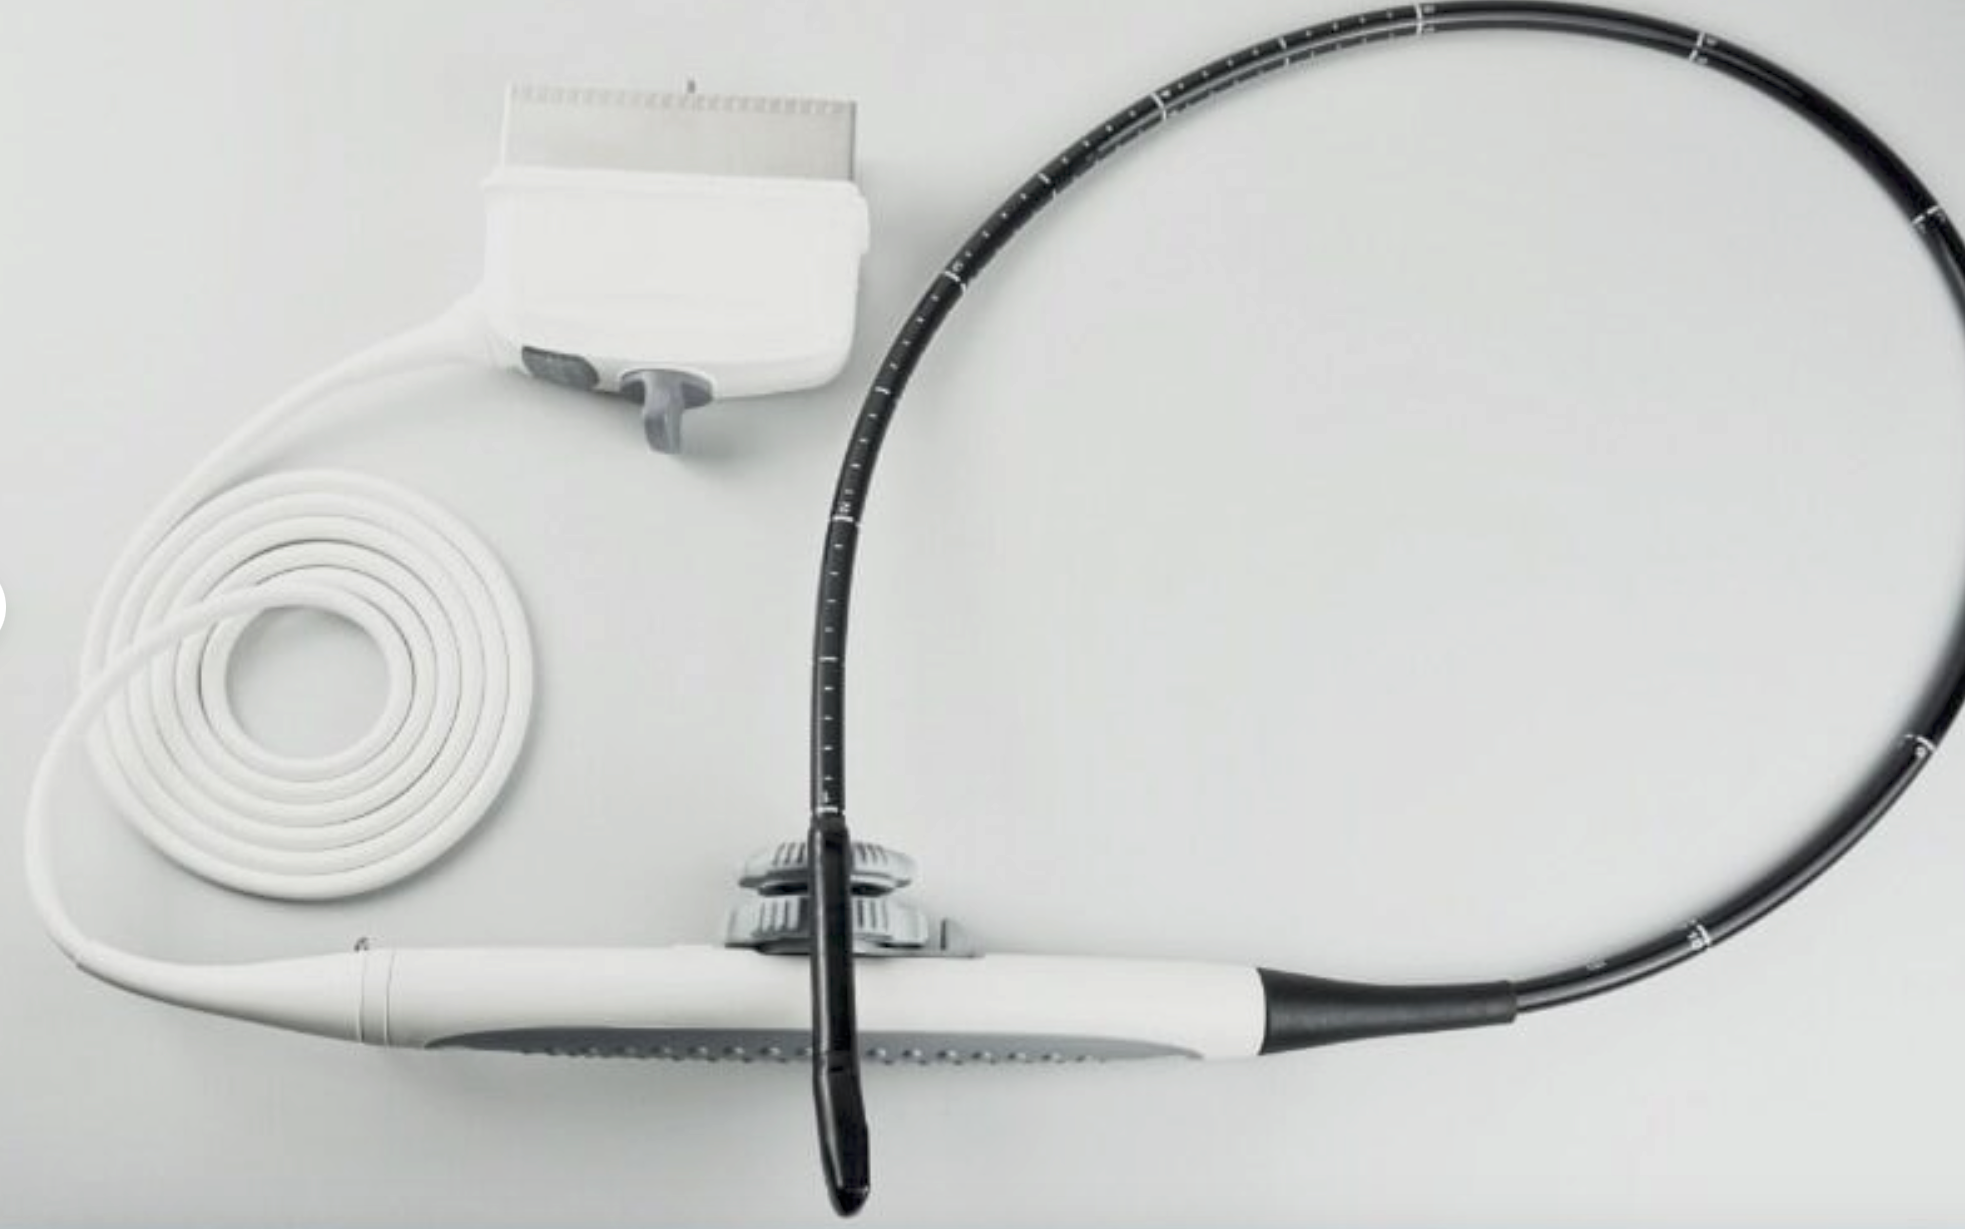

DIAGNOSTIC ULTRASOUND MACHINES FOR SALE

RKU-10 Best Veterinary Handheld Palm Ultrasound Scanner With Rectal Probe & Arm

Sale price$ 4,099.18

Regular price$ 4,999.00